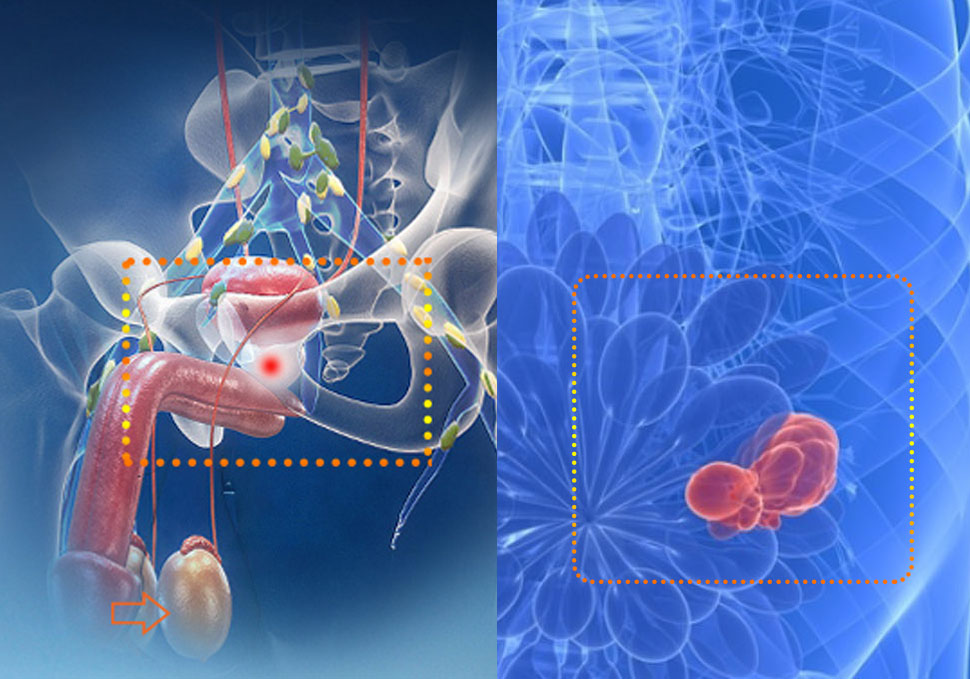

Что такое рак предстательной железы?

– это медленнорастущая злокачественная опухоль, при котором злокачественные клетки формируют опухолевую ткань простаты.